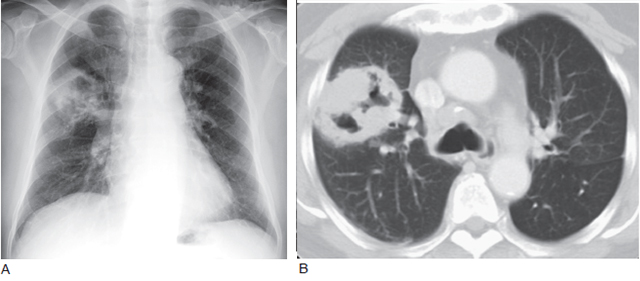

直径超过3cm 的病灶称为肿块(图1,图2,图3)。

A. 胸片显示左肺肿块(M) 提示肺癌,可见双侧胸膜增厚伴钙化(箭头);B.CT 显示左肺肿块(M) 和双侧局限性胸膜钙化斑(箭头),为石棉肺的典型表现